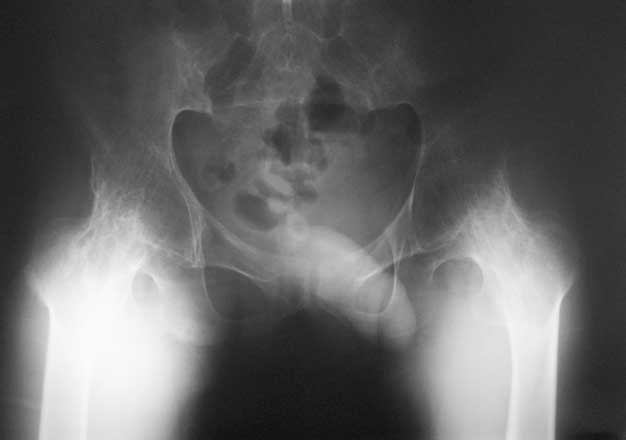

Уважаемые коллеги, в отделении находится пациент 28 лет, страдающий ревматоидным артритом с детства. В настоящее время основной проблемой для него являются тазобедренные суставы - костный анкилоз в положении сгибания около 80 град.

Выраженная атрофия мышц. ограничение движений в коленных суставах.Суставы "замкнулись" со слов пациента около 5 лет назад. Пациент работает (сидячая работа, высшее образование). Все проблемы перечислять не буду. Основное -сложности с ходьбой,самообслуживанием, эстетика и т.д.

Привет Максим. На двух анкилозах передвигаться крайне плохо. Раз ходит - то небольшая часть мышц окружности т.б сустава есть, это видно и на фото. Пошел бы по пути разанкилозирования и бесцементник с каждой стороны поочередно.

Максим, мы протезировали 2х подобных больных. В случае с семилетним анкилозом на фоне болезни Бехтерева функция сустава осталась значительно ограниченой, но больная вполне сносно передвигалась. В другом случае на фоне ревматоидного артрита 4х летний анкизоз у молодого парня получен очень хороший функциональный результат. В обоих случаях использовали бесцементные протезы.

Я бы делал все в один этап, т.к. ситуация по контрактуре не критична. Но при любых анкилозах есть трудности - прежде всего - направление остеотомии шейки бедра. При использовании переднего доступа очень легко ошибиться и "снести" заднюю стенку ВВ, лучше несколько раз перепроверить направление. Обязательно нужно сделать двойную остеотомию для создания необходимого про-ва для обработки ВВ. Необходимо очень не спеша определиться с маркерами ВВ, т.к. обрабатывать впадину Вы будете прямо по головке и иногда бывает сложно понять где находишься. В случае затруднения лучше сделать Р-контроль. В любом случае Вам надо сделать расширенный релиз для достижения хорошей интраоперационной амплитуды движений. И последнее - многие пациенты остаются неудовлетворенными р-ми операции из-за чувства нестабильности, "провала" в суставе, выраженной хромоты. Это связано с длительным бездействием мышц. Это не значит, что не надо делать операции, просто это надо иметь ввиду и объяснять пациентам.

Полностью согласен с Р.Тихиловым, что операцию необходимо делать за один этап. Однако, возможно, стоит учесть некоторые моменты:

1) Риск получения нейропатии бедренного нерва в данной ситуации действительно очень высок. В послеоперационном периоде необходима укладка со сгибанием в тазобедренном суставе не менее 50% от исходного, при этом сгибание в коленном суставе должно быть минимальным (мой опыт показывает, что наиболее безопасно положение как на шине Бел.). Далее постепенное уменьшение разгибания.

2) Щадящая и контролируемая разработка тазобедренного сустава: исходно при анкилзе тазобедренного сустава вся нагрузка распределяется по кортикальным пластинкам, а губчатая кость (хоть это и бывшая головка бедренной кости) исключена из нагрузочного процесса и следовательно не готова к компрессионным нагрузкам, что приводит к высокому риску ранней ассептической нестабильности вертлужной впадины.